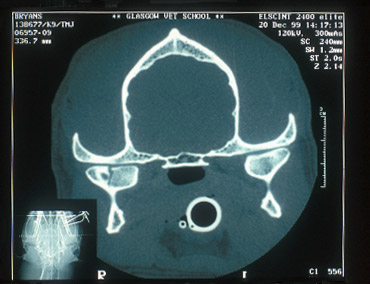

CT scan of fractured right mandibular

condyle

X-ray & CT images

courtesy of Glasgow University

Advantages

- Provides powerful images and computer reconstruction of

otherwise hard to examine areas, such as TMJ's, caudal mandibular

body, coronoid process and zygomatic arch